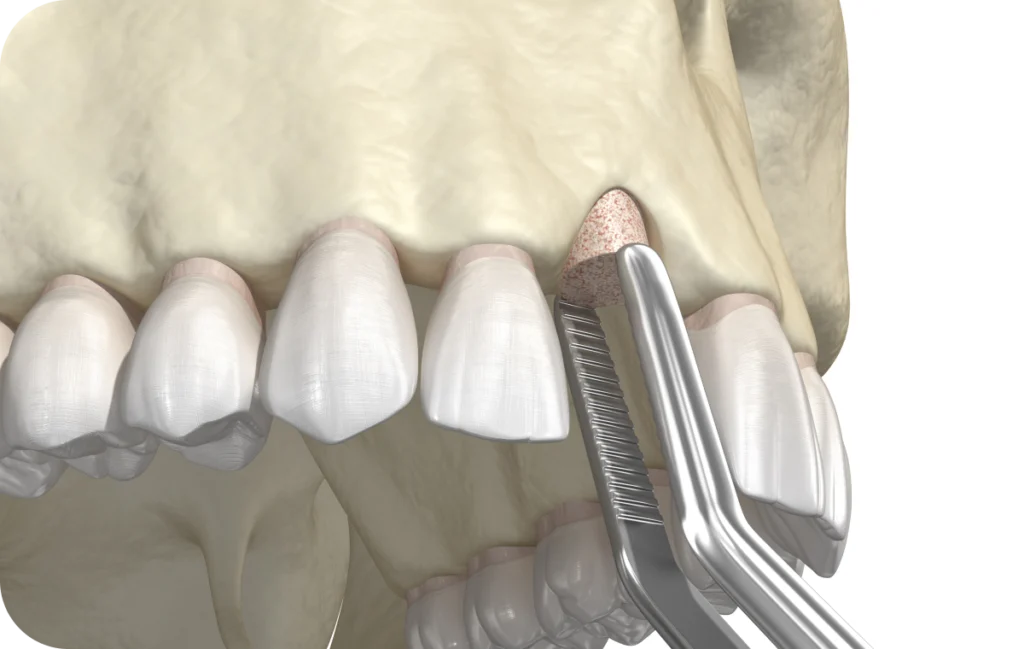

La greffe osseuse est un acte chirurgical qui vise à recréer ou renforcer le volume osseux de la mâchoire. Elle s’effectue avant, ou parfois en même temps que la pose d’un implant dentaire. Le principe est simple : combler le déficit osseux par un matériau (provenant du patient, d’un donneur, d’origine animale ou de synthèse) afin de recréer un socle solide et durable.

La greffe osseuse se distingue des extractions ou des chirurgies gingivales par son objectif de reconstruction. Là où d’autres interventions visent à retirer ou soigner, la greffe a pour but de reconstruire et régénérer l’os alvéolaire.

Elle consiste à prélever un fragment osseux sur le patient, souvent au niveau du menton ou de la mandibule.

Étapes de l’intervention

- Anesthésie locale, parfois associée à une sédation,

- Incision et préparation du site receveur,

- Mise en place et stabilisation du greffon,

- Fermeture avec des sutures résorbables ou non.